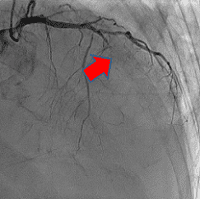

経皮的冠動脈インターベンションの一例

-

- 【1】術前

- 【2】ワイヤー通過

- 【3】ステント留置

- 【4】術後